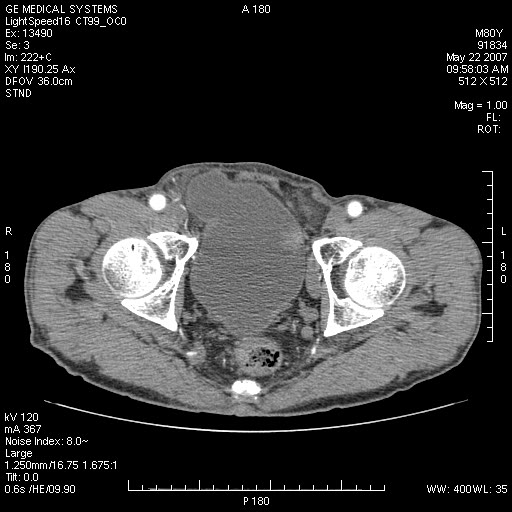

标题: CT8346:男,80岁。血尿,肝脏,膀胱占位,是否为肝转移?

男,80岁。血尿,无腹部不适病史。

膀胱病变:

增强原原发性肝癌、膀胱癌伴左侧盆腔淋巴转移。

可能为双原发,肝癌,膀胱癌.盆腔淋巴结转移!

肝脏内病灶有假包膜,增强扫描动脉期有动静脉瘘,有快进快出特点,考虑原发性肝癌。病灶内有裂隙样低密度影,以纤维板层样细胞癌可能性大。膀胱左侧乳头状占位,增强呈明显强化,左侧盆腔内有肿大淋巴结,结合有血尿病史,考虑膀胱癌左侧盆腔淋巴结转移。